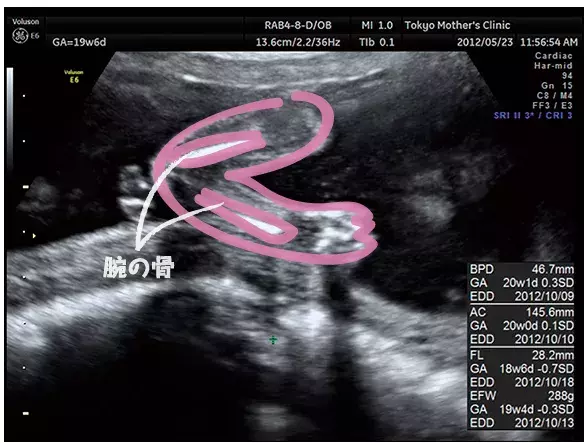

妊娠19週のエコー写真

腕を曲げた様子、指の様子もはっきり分かるエコー写真。骨は白く写るので分かりやすい。

写真提供:東京マザーズクリニック